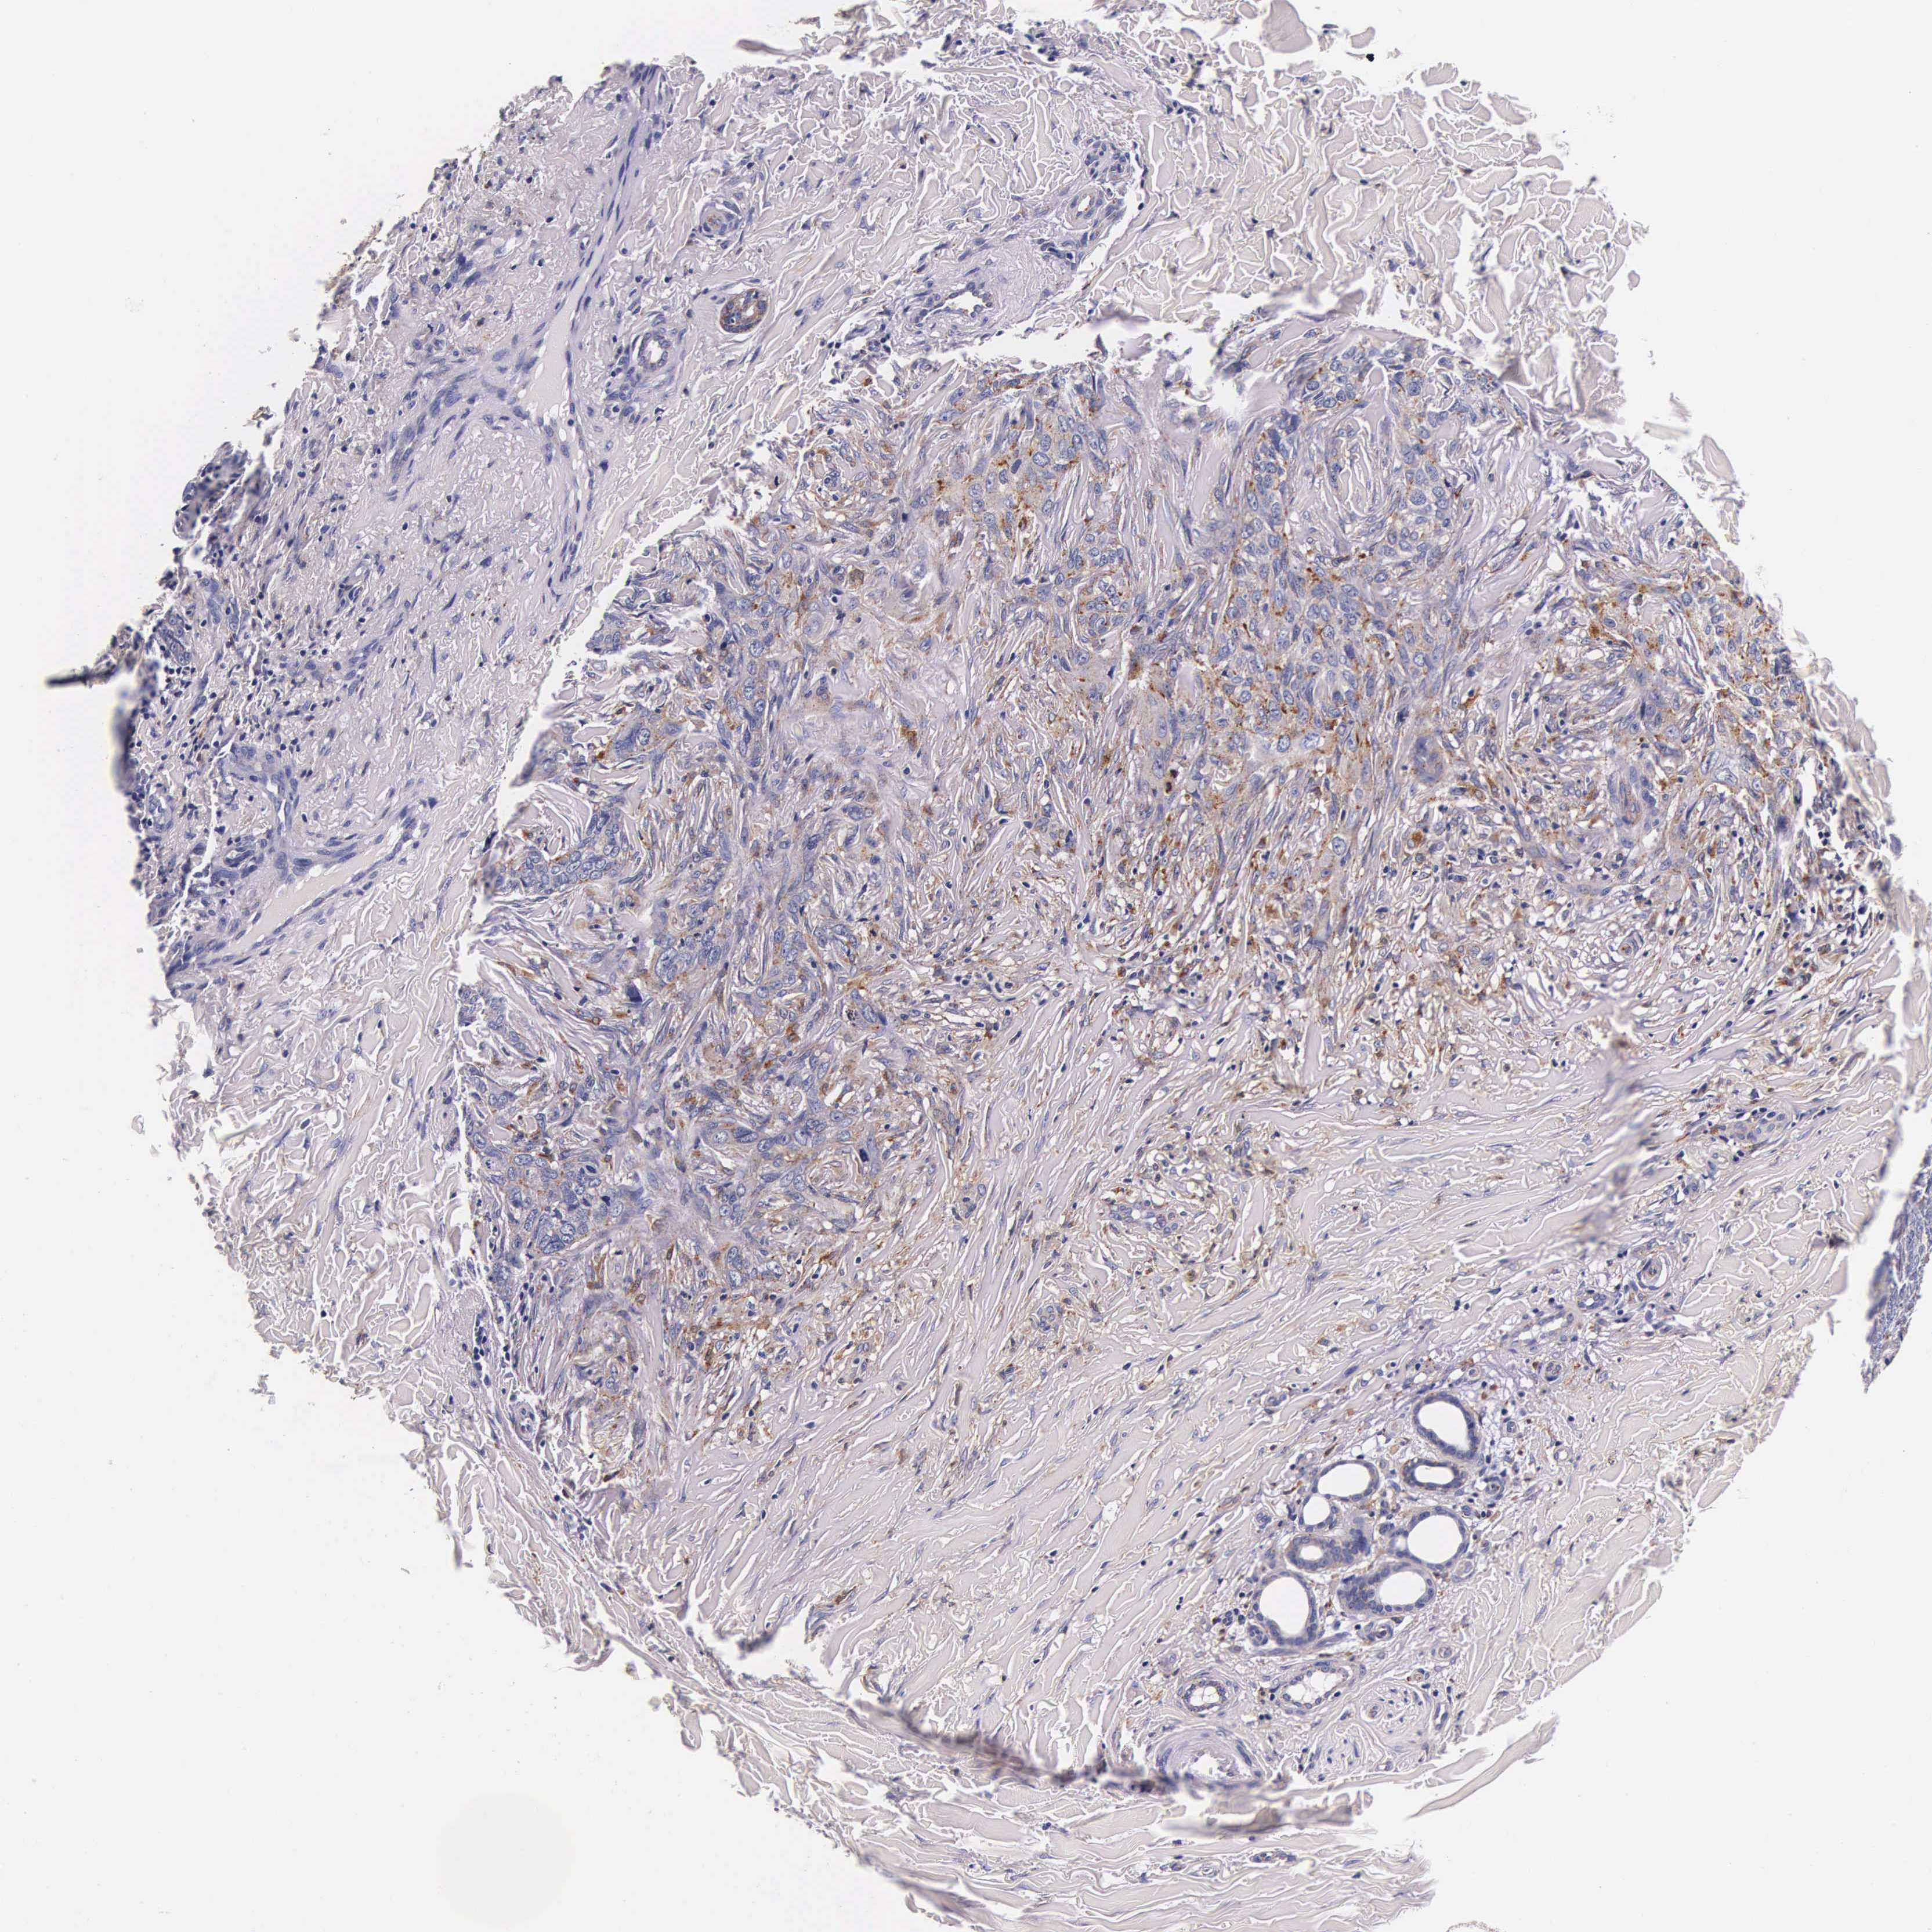

SKIN CANCER - Protein expressioni

A mouse-over function shows sample information and annotation data. Click on an image to view it in a full screen mode. Samples can be filtered based on level of antibody staining by selecting one or several of the following categories: high, medium, low and not detected. The assay and annotation is described here.

Antibody stainingi

Antibody staining in the annotated cell types in the current human tissue is reported as not detected, low, medium, or high, based on conventional immunohistochemistry profiling in selected tissues. This score is based on the combination of the staining intensity and fraction of stained cells.

Each image is clickable and will lead to virtual microscopy that enables deeper exploration of all samples and also displays staining intensity scores, fraction scores and subcellular localization as well as patient and tissue information for each sample.

Antibody CAB000457